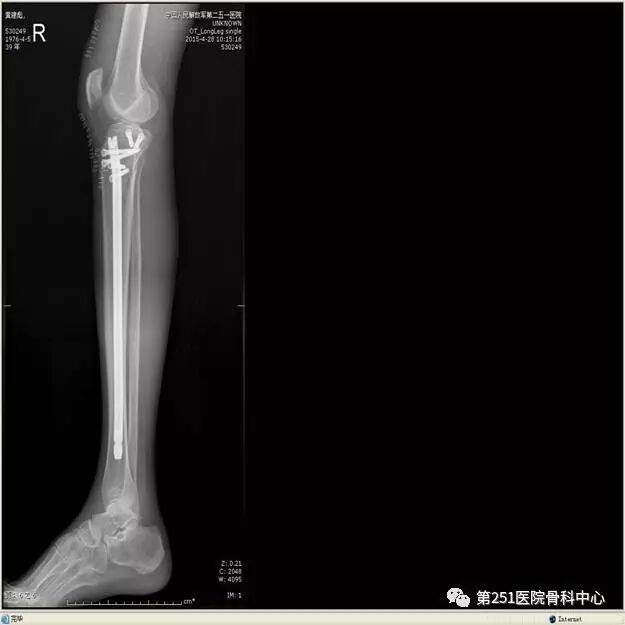

病例6:男性,39岁,车祸伤SchatzkerⅥ型胫骨平台骨折。